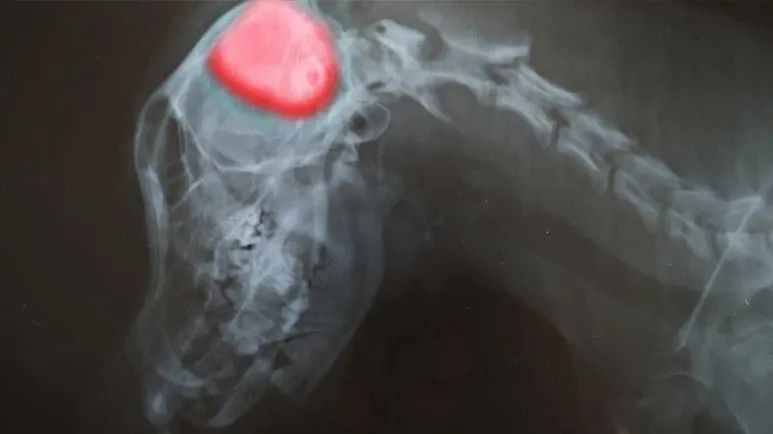

- Diagnosis typically requires advanced imaging like MRI or CT scans, and treatment options include surgery, radiation therapy, medications, and promising new immunotherapy approaches

A meningioma is the most common form of primary brain tumor found in dogs. It accounts for approximately 50% of brain tumors in dogs and 85% of brain tumors in cats.1 However, a meningioma arises not from the brain tissue itself, but from the meninges — the protective membranes surrounding the brain and spinal cord. Although these tumors are generally classified as benign, their growth can exert pressure on the brain, leading to significant neurological complications.2,3

If your dog is over 6 years old and begins showing these signs, particularly seizures or confusion, it is best to consult your integrative veterinarian immediately. Your vet will typically conduct a comprehensive physical and neurological exam to identify if there is a neurological disorder. Specific diagnostic tests may also help determine if a brain tumor is present, such as blood tests, ultrasound, X-ray, MRI, CT scan, biopsy, or spinal fluid analysis.